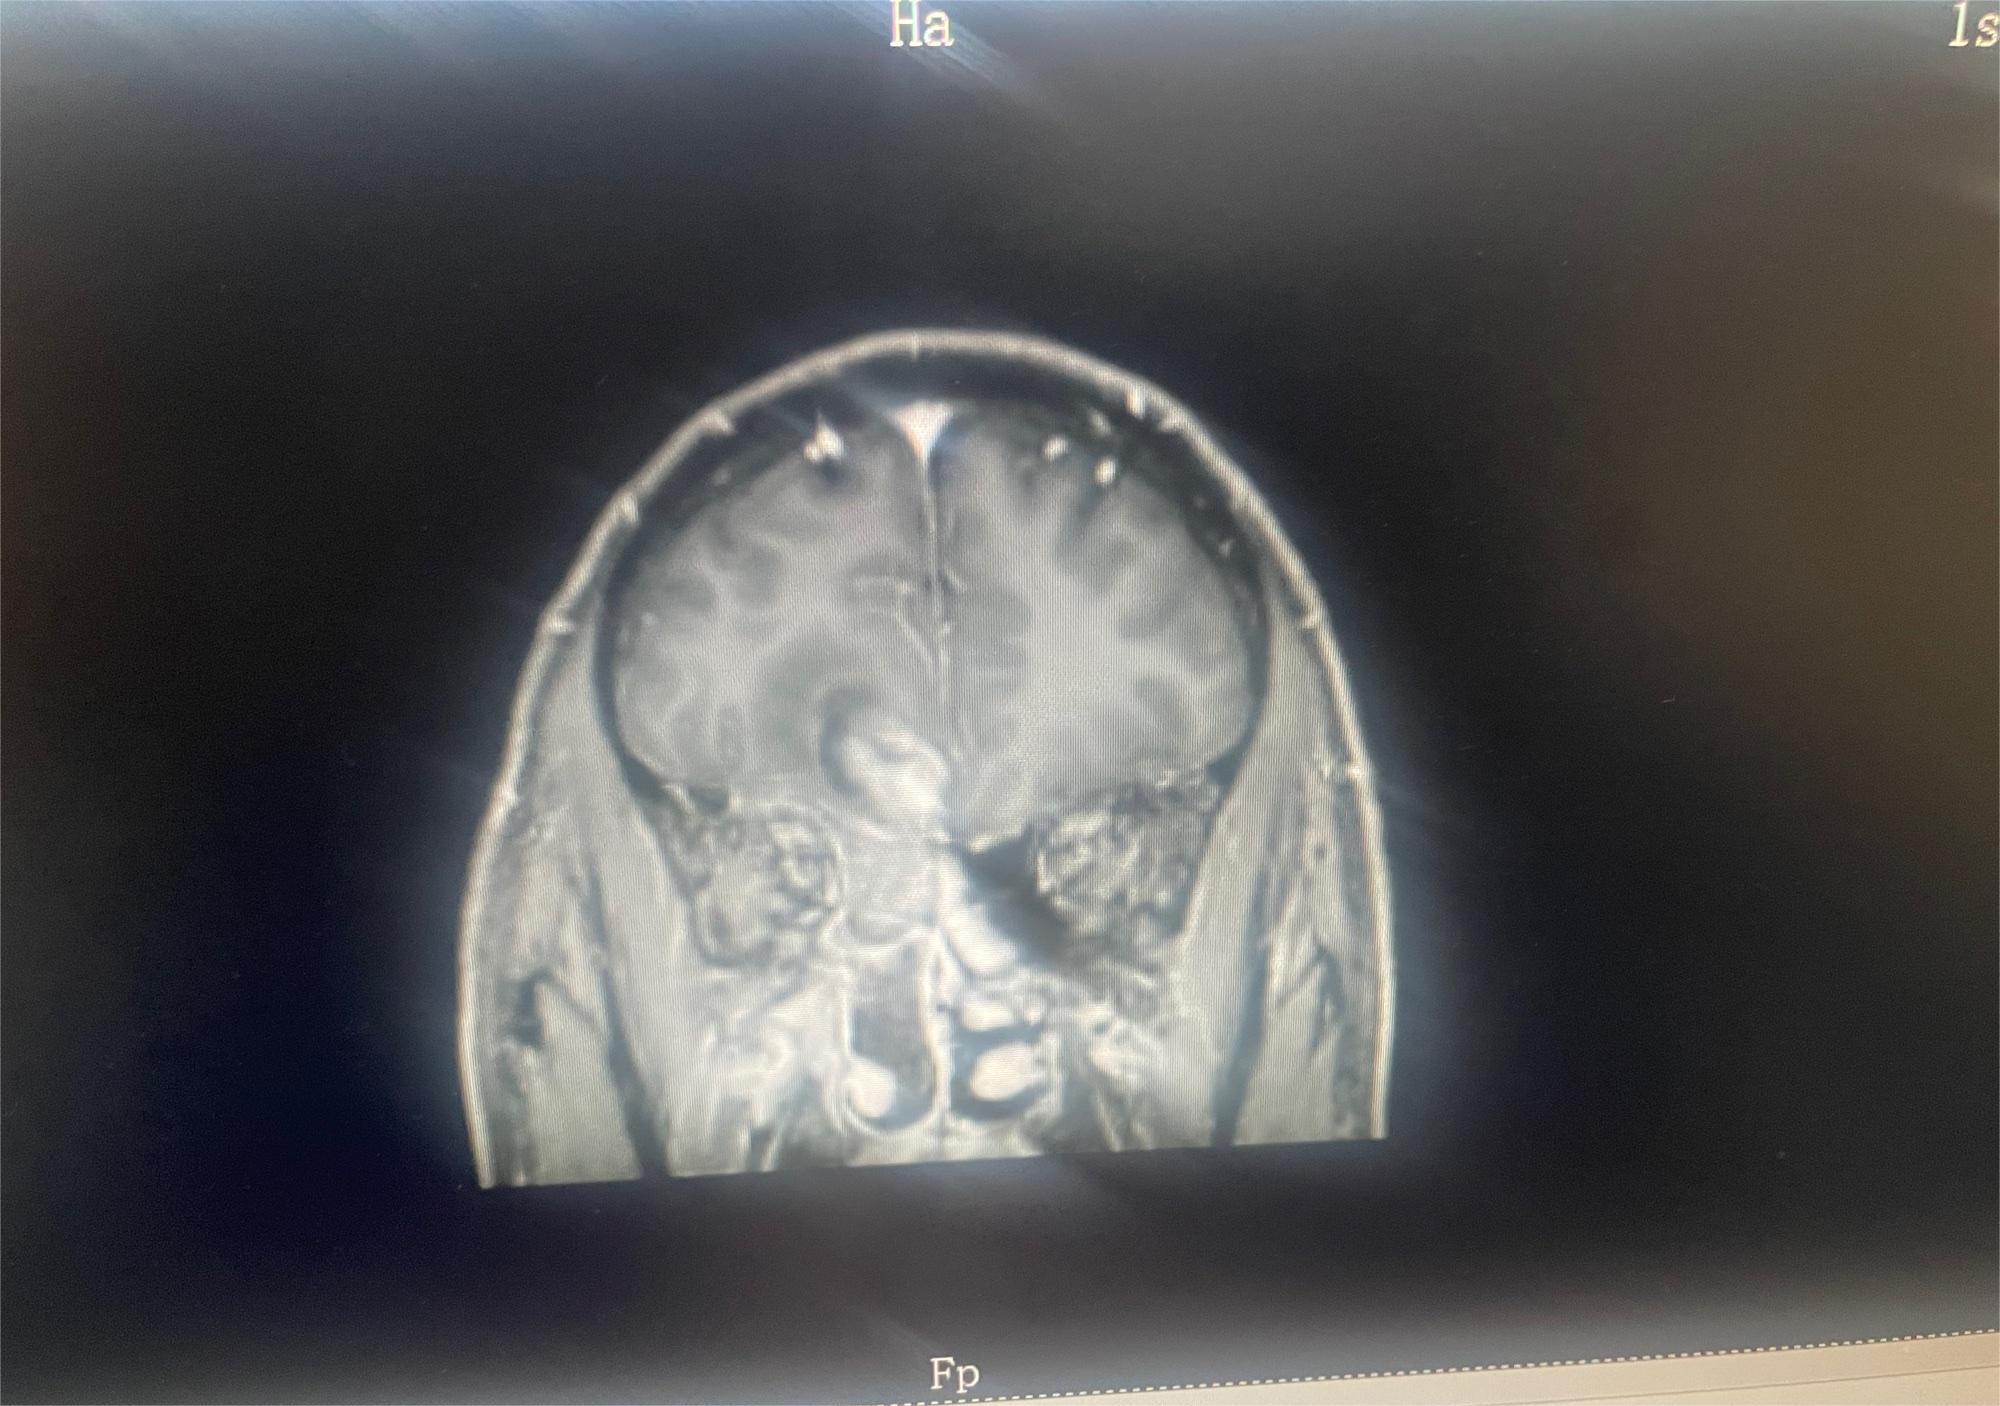

求助有没有比较好医院或者治疗好的方案

共1张

脑部肿瘤求助